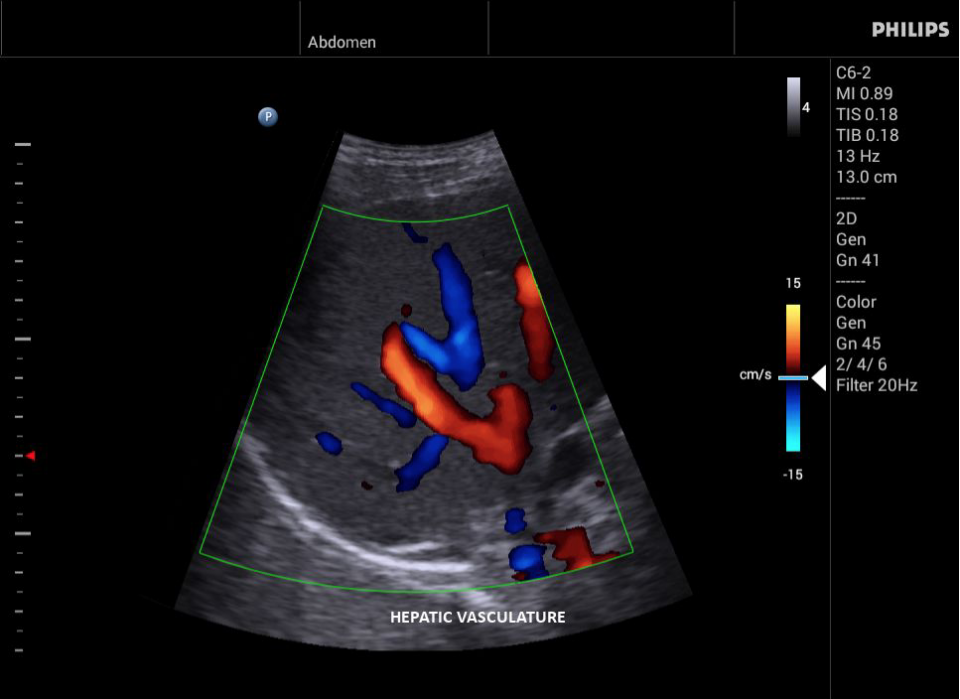

Philips InnoSight

Philips InnoSight увеличивает возможности сканирования во множестве мест оказания медицинских услуг. Благодаря данному УЗИ аппарату врачи могут не сомневаться в быстром выполнении обычных ультразвуковых сканирований во врачебном кабинете, клинике или больнице.

• Цветное допплеровское картирование

• Конвексный УЗИ датчик Philips C9-4v

• Конвексный УЗИ датчик Philips С6-2